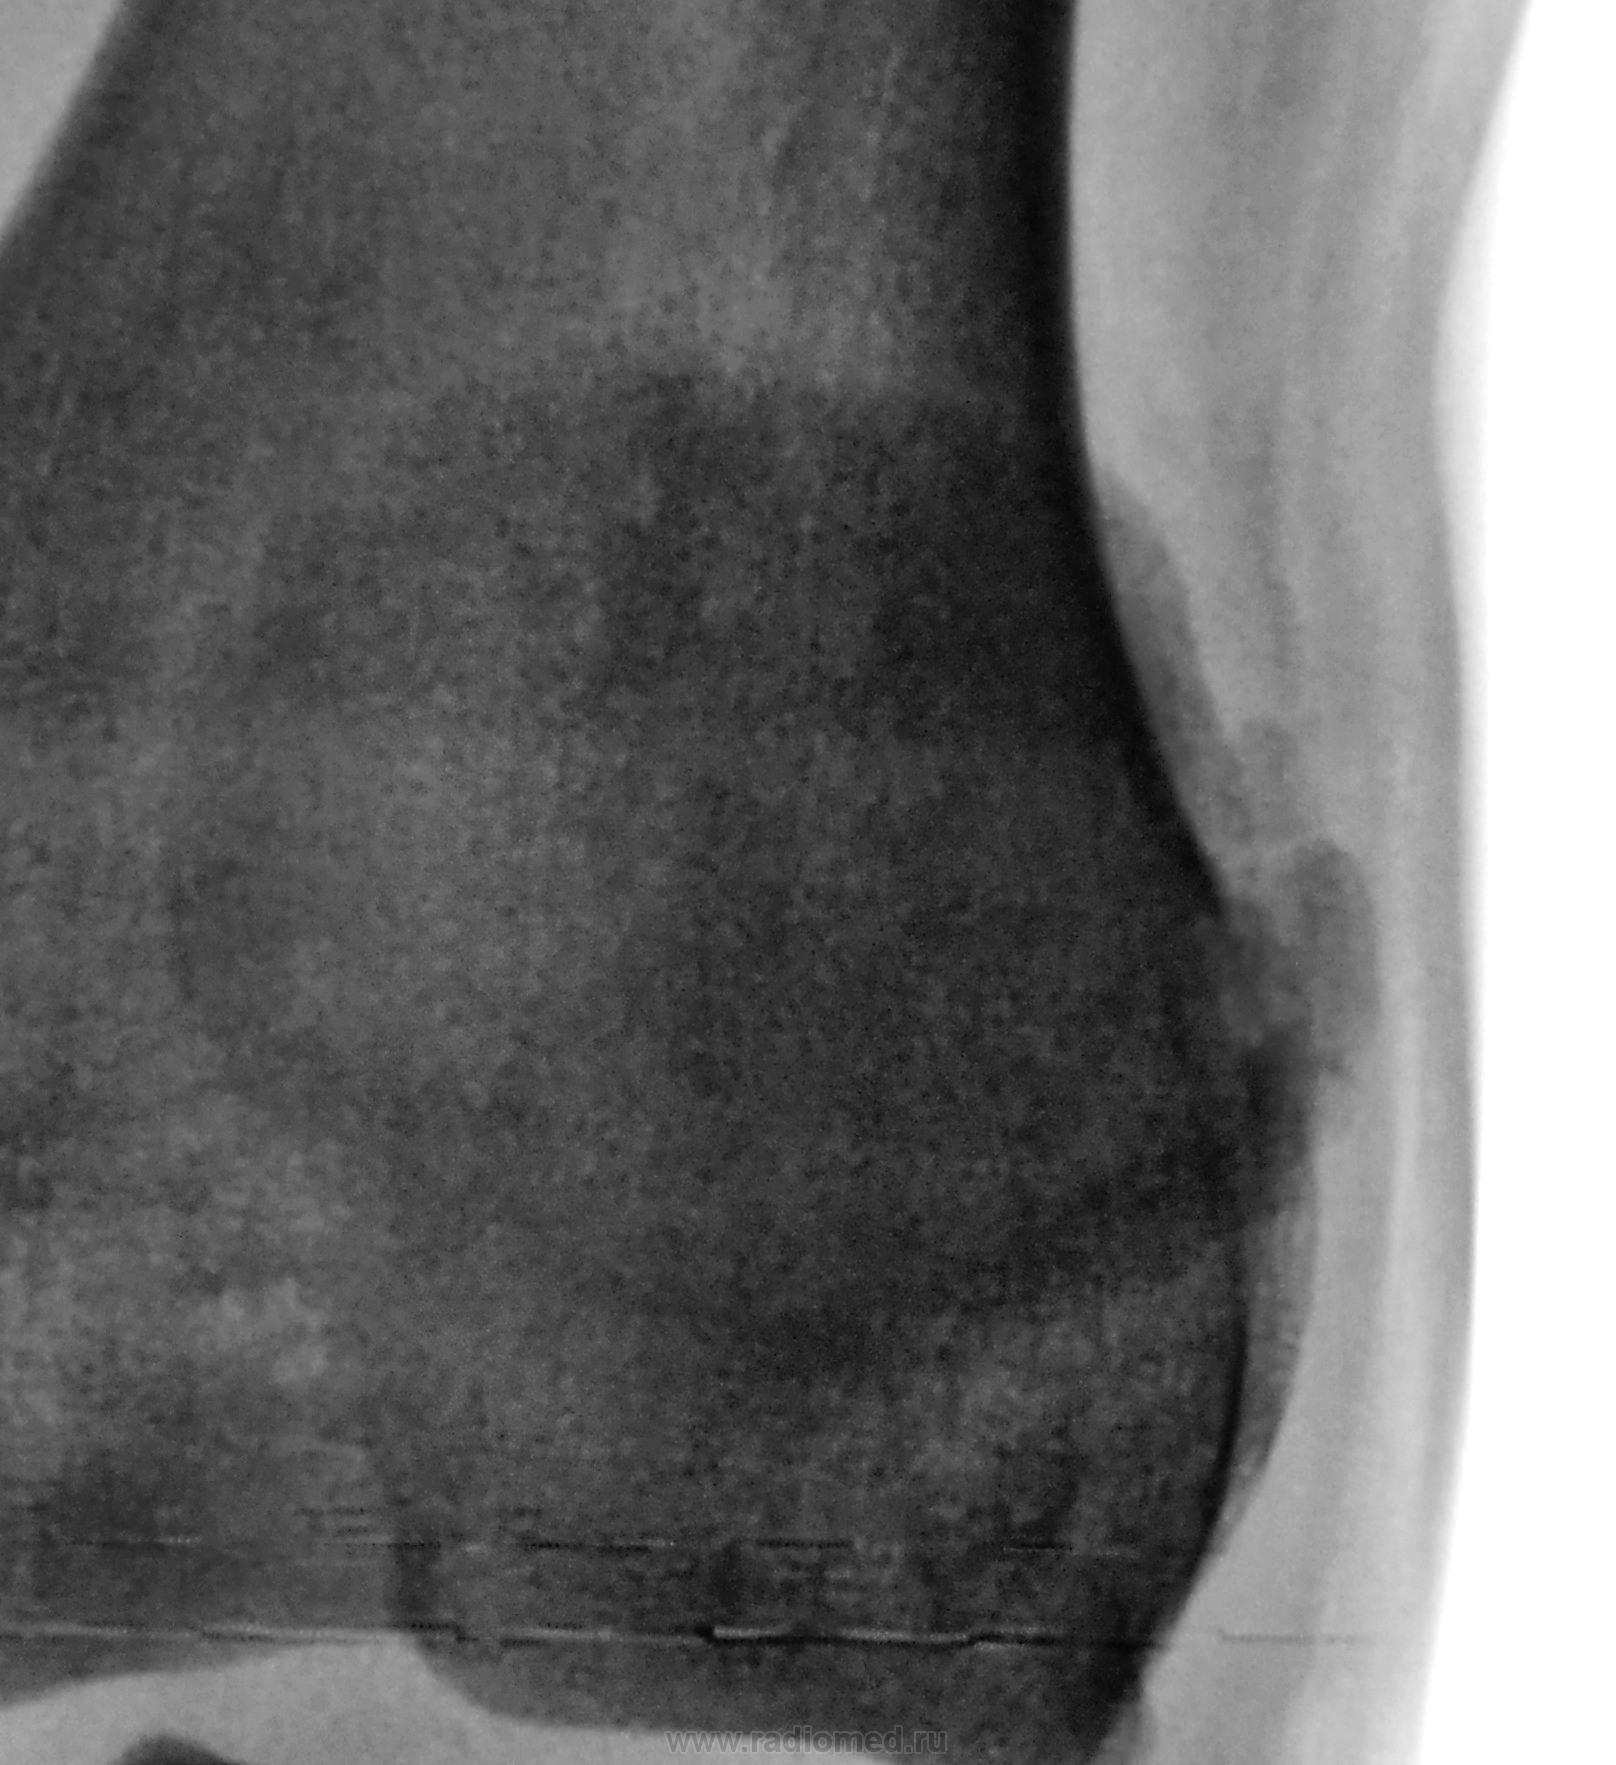

Направлен был традиционно из военкомата для рентгенографии стоп и позвоночника. Но лаборант заметил, что "клиент" полностью, в положении лёжа, ноги в коленных суставах не разгибает. Решили дополнительно "снять" коленные суставы...

Дисплазия это...

Похоже+дольчатое строение надколенников.

Кажущаяся нестабильность надколенников (их латерализация) связана с укладкой, или же это одно из проявлений дисплазии?

Как на ваш взгляд - это "вакуум-феномен"?

ДА! И еще какой!

Можно было бы обозвать его - "диспластическим", в такой ситуации встречаюсь впервые))))

МРТ полностью подверждает дисплазию

Эпифизарная дисплазия.